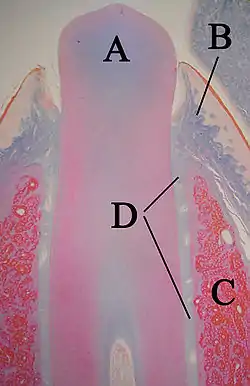

A: enamel organ

B: dental papilla

C: dental follicle

The tooth germ is an aggregation of cells that eventually forms a tooth.[2] These cells are derived from the ectoderm of the first pharyngeal arch and the ectomesenchyme of the neural crest.[1][3][4] The tooth germ is organized into three parts: the enamel organ, the dental papilla and the dental sac or follicle.

The enamel organ is composed of the outer enamel epithelium, inner enamel epithelium, stellate reticulum and stratum intermedium.[2] These cells give rise to ameloblasts, which produce enamel and become a part of the reduced enamel epithelium (REE) after maturation of the enamel. The location where the outer enamel epithelium and inner enamel epithelium join is called the cervical loop.[1] The growth of cervical loop cells into the deeper tissues forms Hertwig Epithelial Root Sheath, which determines the root shape of the tooth. During tooth development there are strong similarities between keratinization and amelogenesis.[5][6] Keratin is also present in epithelial cells of tooth germ [7] and a thin film of keratin is present on a recently erupted tooth (Nasmyth's membrane or enamel cuticle).[8]

The dental papilla contains cells that develop into odontoblasts, which are dentin-forming cells.[2] Additionally, the junction between the dental papilla and inner enamel epithelium determines the crown shape of a tooth.[1] Mesenchymal cells within the dental papilla are responsible for formation of tooth pulp.

The dental sac or follicle gives rise to three important entities: cementoblasts, osteoblasts, and fibroblasts. Cementoblasts form the cementum of a tooth. Osteoblasts give rise to the alveolar bone around the roots of teeth. Fibroblasts are involved developing the periodontal ligament which connect teeth to the alveolar bone through cementum.[9]